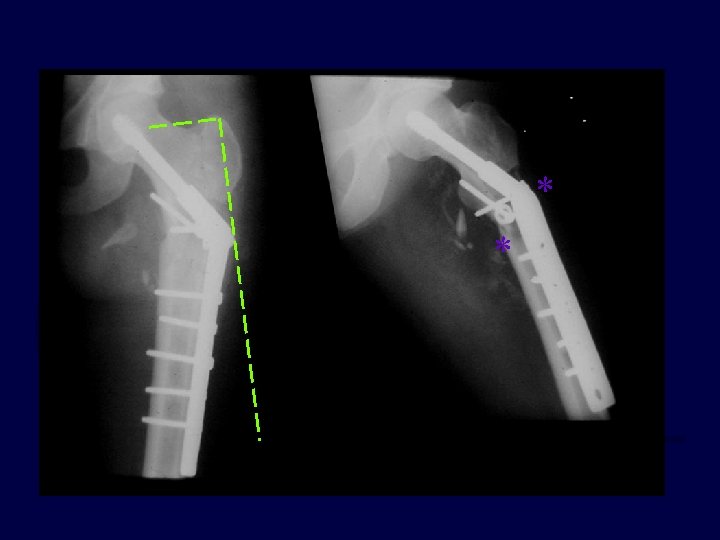

* *

Progressive pain 11 -14 weeks (varus + plate is rarely good)